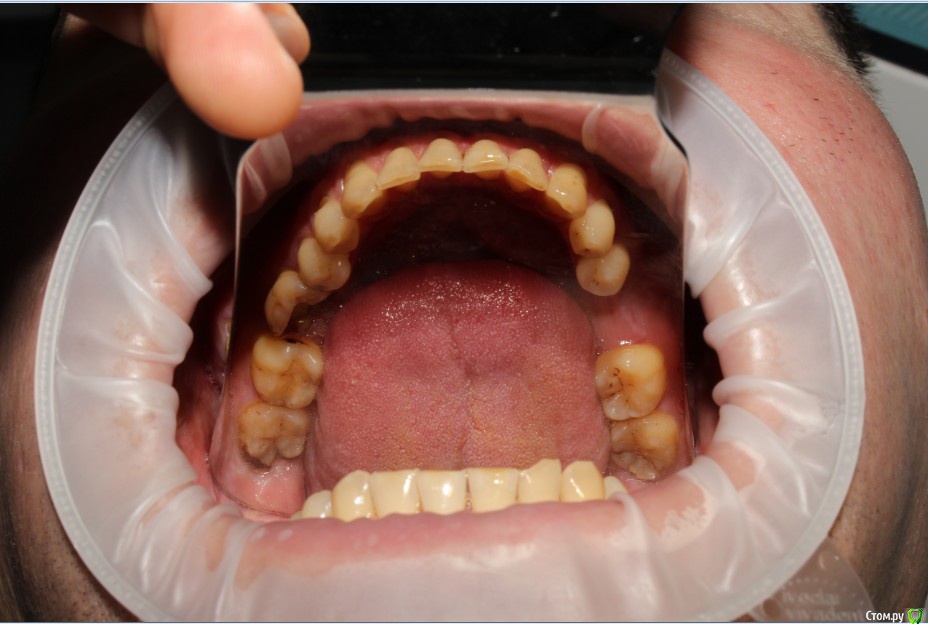

Рустам Опубликовано 20 июля, 2015 Поделиться Опубликовано 20 июля, 2015 Здравствуйте коллеги! Подскажите по клиническому случаю пожалуйста. Обратился пациент в клинику с подвижной коронкой на зубе 2.1, на рентгене диагностирован перелом корня, планируем удаление с одномоментной имплантацией и желательно с немедленной нагрузкой. Система имплантатов "Osstem", на этой системе я ранее не протезировал (работал с "Mis" и "Super Line") и вообще ранее немедленно не нагружал имплантаты. Хирург назначил удаление и иплантацию на 23.07, я смогу принять пациента только 24.07 утром, необходимо заказать временный абатмент, подскажите какой именно из каталога нужно заказать?Имплантолог заказал два имплантата Osstem TSIII SA диаметром 4,0 и 4,5.Я планирую делать временную прямым способом по ключу снятому со старой коронки во рту. Может лучше через оттиск заказать лабораторную временную?P.S. пациента эстетически все устраивало, ортодонтию не хочет. Ссылка на комментарий